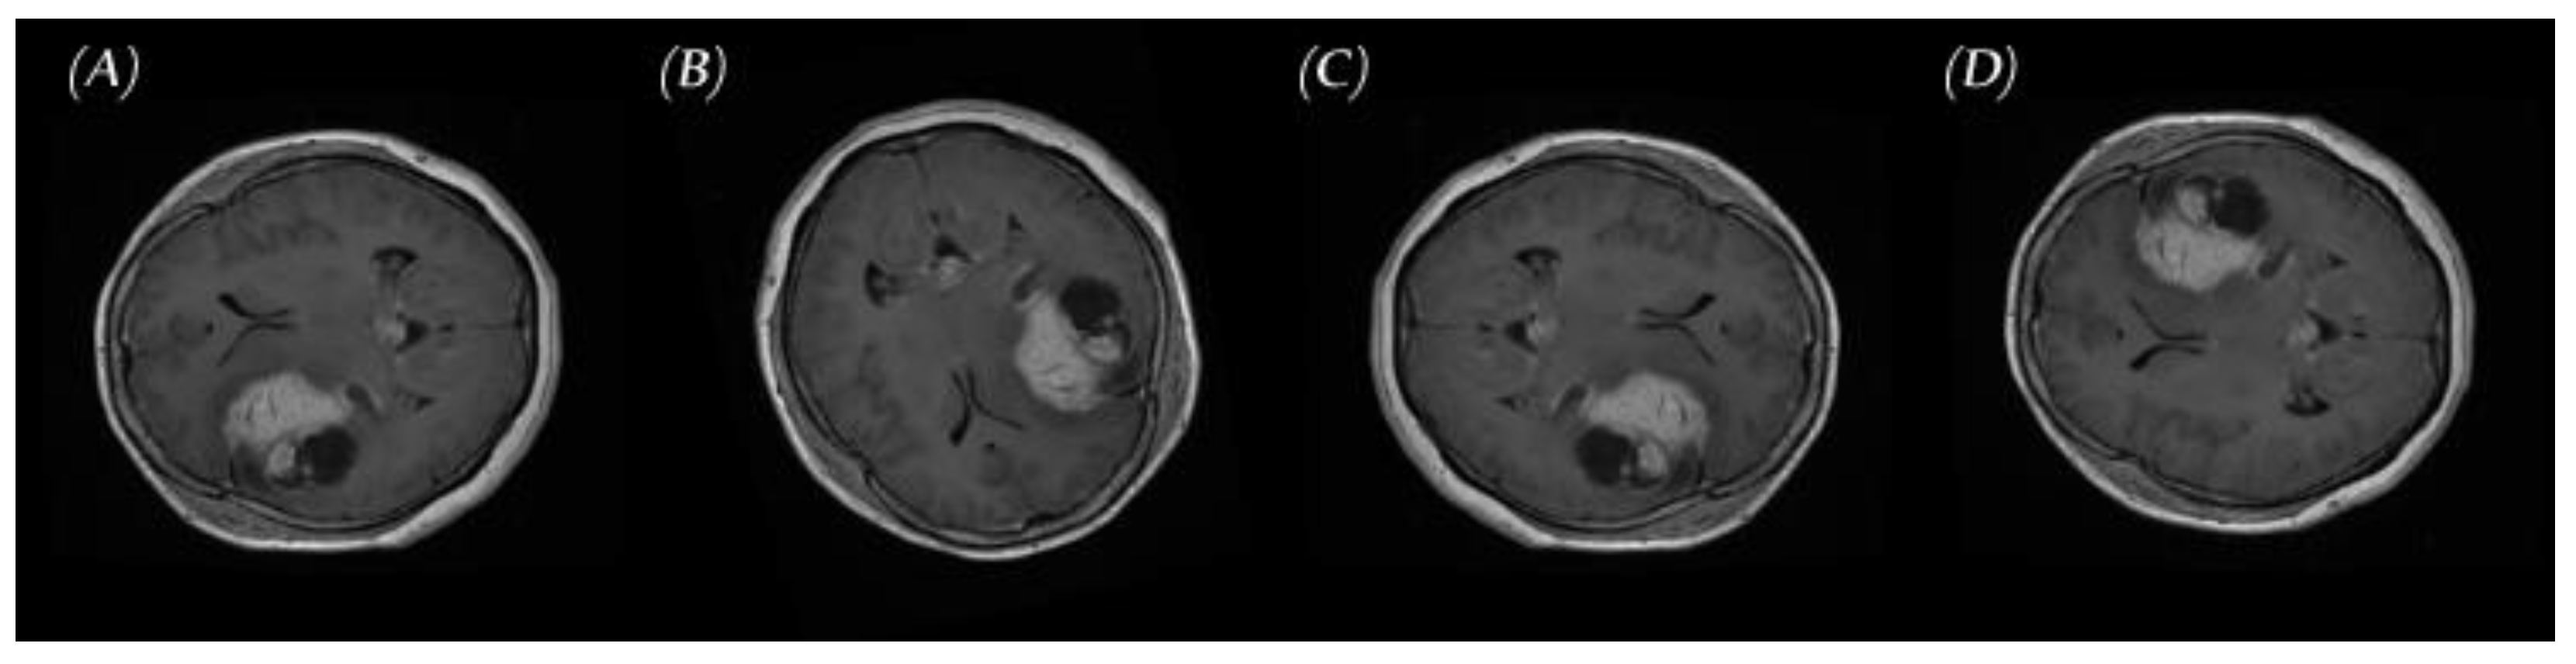

2.1. Data set for the Study

2.2.2. PGGAN-Based Data Augmentation